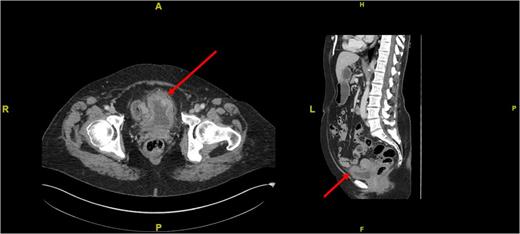

We embarked on close endoscopic surveillance and six weeks later a rigid cystoscopy revealed a 6 cm solid recurrence at the previous resection site. This was completely resected and histopathological analysis again confirmed IMT recurrence with ALK1 gene rearrangement. Due the low reported incidence of metastases bladder conservation was the preferred option but since it recurred so quickly we opted for partial cystectomy. A further pelvic magnetic resonance imaging (MRI) performed 4 weeks post-op demonstrated 22 mm × 10 mm irregular area with associated increased enhancement involving the left anterolateral wall of the bladder which in keeping with the site of the primary resection and no evidence of locally advanced disease (Fig. 3).

Sagittal MRI image of the pelvis showing irregularity in the anterolateral bladder wall at the site of resection (see red arrow).